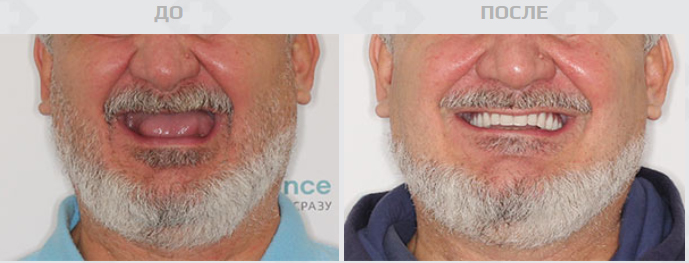

Лишних хлопот можно избежать, если воспользоваться услугами проверенной клиники и провести имплантацию по протоколу немедленной нагрузки. Это значит, что пациенту установят несъемный зубной протез в течение 2-3 дней после вживления имплантатов. Уникальность в том, что жевательная и эстетическая функции зубов будут восстановлены полностью почти мгновенно. Как правило, костная пластика при таком методе не требуется. Так весь процесс лечения вместе с подготовкой займет не более одной недели.

Немедленную нагрузку рекомендуют в основном при множественном или при полном отсутствии зубов. Процедуру можно проводить в любом возрасте при отсутствии общих противопоказаний. Прибегнуть к такой имплантации можно при воспалении пародонта и костной ткани, а также при проседании челюстной кости, которая неизбежно возникает после потери живых зубов.

Имплантация — то, на что бывает сложно решиться, но большинство после процедуры признаются, что зря откладывали поход к врачу так долго. Буквально за несколько дней удастся обзавестись ослепительной улыбкой, снова почувствовать вкус любимой пищи и вернуть себе незабываемое ощущение здоровья полости рта. Реабилитация при удачном исходе проходит максимально быстро. Это важно в том числе — для работающего населения. Для того, чтобы сделать имплантацию, не придется бросать дела или брать долгосрочный отпуск.

В клинике без труда проведут всю работу за несколько дней благодаря качественному оборудованию и высококлассным специалистам. Пациента окружат заботой и вниманием и сориентируют, какой из методов немедленной нагрузки лучше выбрать, какой из вариантов будет самым оптимальным и долговечным.

Среди остальных Smile-at-Once выделяет наличие качественной 3D диагностики. Именно она помогает избежать ошибок и грамотно справиться даже с самыми сложными случаями. Специалисты и виртуально, и реально прорабатывают процесс лечения, создают модели челюсти и шаблоны. Так удается в точности повторить не только строение челюсти, но и плотность костных тканей.